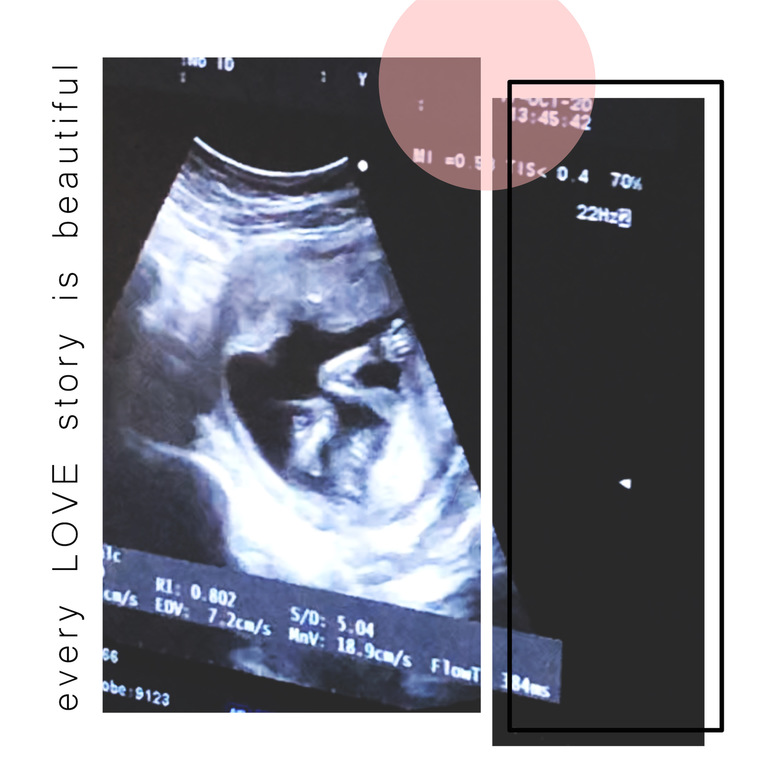

Девочка🥰

Пол малышаПривет, принцесса 👸🏼 Как мы чувствовали, как знали, что в животике у меня девочка❤️🙏🏼 На узи меня крутили и вертели, малышка пиналась, а я не чувствовала😁

Привет, принцесса 👸🏼 Как мы чувствовали, как знали, что в животике у меня девочка❤️🙏🏼 На узи меня крутили и вертели, малышка пиналась, а я не чувствовала😁